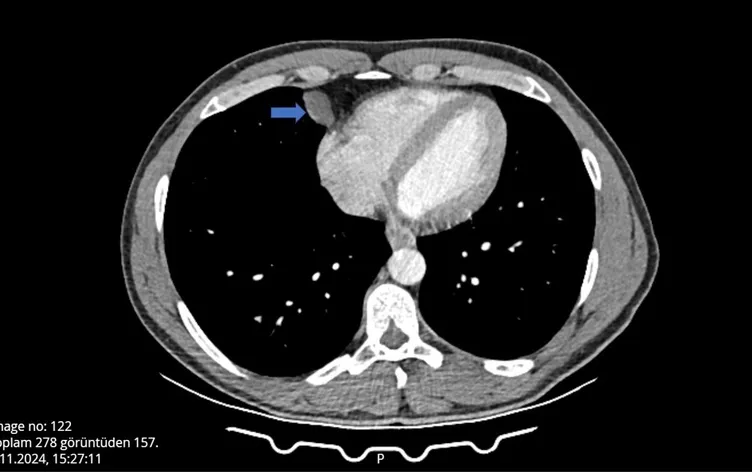

Burada tomografisi çekilen Can’ın, akciğer ile kalbinin arasında bir kist olabileceği belirtildi. Can, çevresindekilerin tavsiyesi üzerine detaylı araştırma ve inceleme için, Antalya Eğitim ve Araştırma Hastanesine başvurdu.

Gerekli tetkikleri yapılan Ömer Can’ın, belirtilen bölgesinde yaklaşık 2 santimlik bir kist olduğu tespit edildi ve hemen ameliyata alındı.

Göğüs Cerrahi bölümünde Video Yardımlı Torakoskopik Cerrahi (VATS) yöntemiyle gerçekleşen ameliyat yaklaşık 10 dakika sürdü.